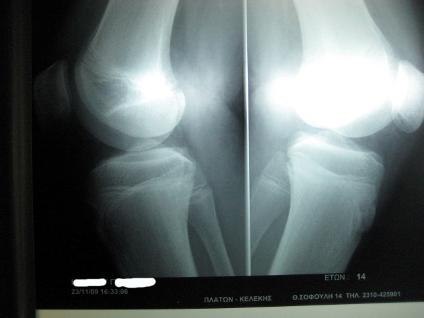

Σύνδρομο Osgood-Schlatter σε νεαρό αθλητή |

Ακτινογραφία 23-11-2009. Αμέσως μετά την θεραπεία |